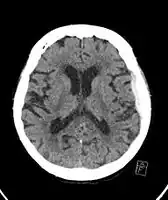

| Subdural hematoma as marked by the arrow with significant midline shift | |

Subdural hematomas occur most often around the tops and sides of the frontal and parietal lobes.[9][10] They also occur in the posterior cranial fossa, and near the falx cerebri and tentorium cerebelli.[9] Unlike epidural hematomas, which cannot expand past the sutures of the skull, subdural hematomas can expand along the inside of the skull, creating a concave shape that follows the curve of the brain, stopping only at dural reflections like the tentorium cerebelli and falx cerebri.

On a CT scan, subdural hematomas are classically crescent-shaped, with a concave surface away from the skull. However, they can have a convex appearance, especially in the early stages of bleeding. This may cause difficulty in distinguishing between subdural and epidural hemorrhages. A more reliable indicator of subdural hemorrhage is its involvement of a larger portion of the cerebral hemisphere. Subdural blood can also be seen as a layering density along the tentorium cerebelli. This can be a chronic, stable process, since the feeding system is low-pressure. In such cases, subtle signs of bleeding—such as effacement of sulci or medial displacement of the junction between gray matter and white matter—may be apparent.